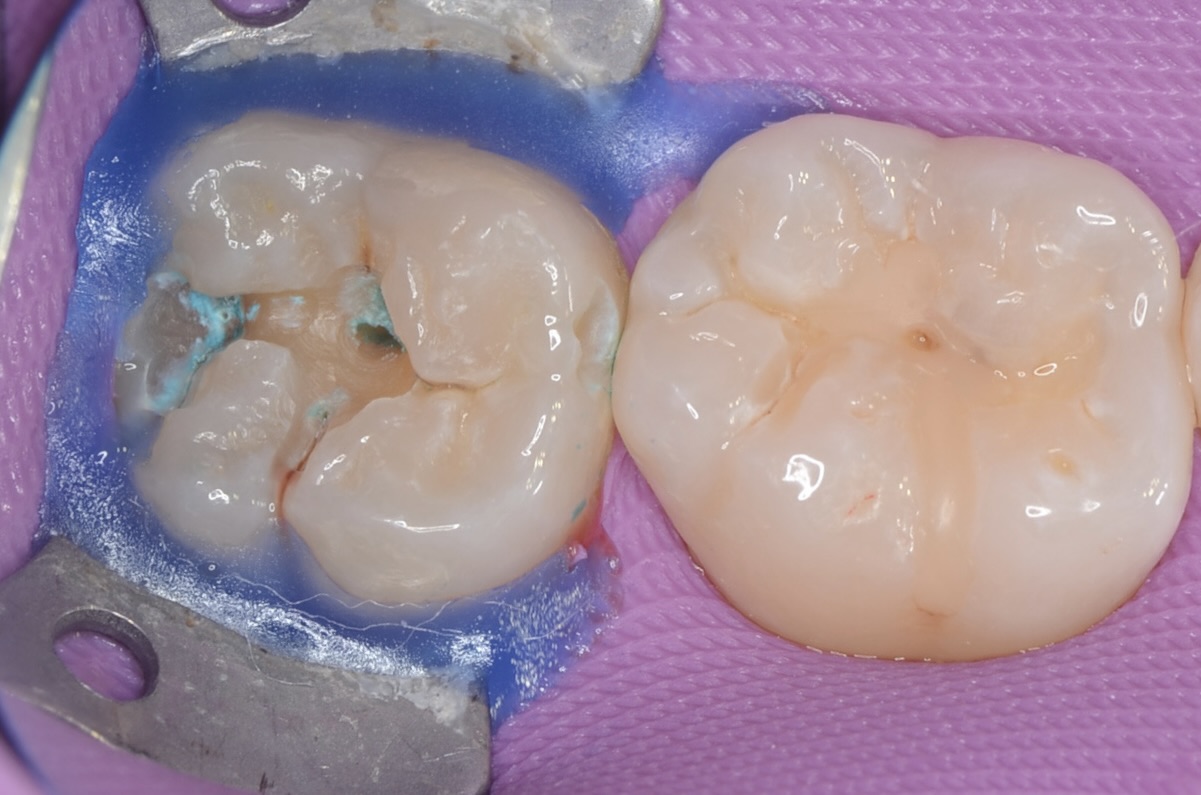

ラバーダム装着

虫歯治療においてもラバーダム装着は必須です。 唾液や血液から歯面が汚染されるのを防ぎ、乾燥状態を保つラバーダムは、接着力を向上させるためにも大切なアイテムです。 虫歯になっている歯は一部歯茎が被さっています。ラバーダムが装着しにくくラバーの隙間から唾液が侵入しそうだったので青い柔らかいレジンで隙間を埋めました。 -

ラバーダム装着後、虫歯をとる

少し歯を削って齲蝕検知液で染めてみると青く染まります。やはり歯の中で虫歯が進行しています。 -